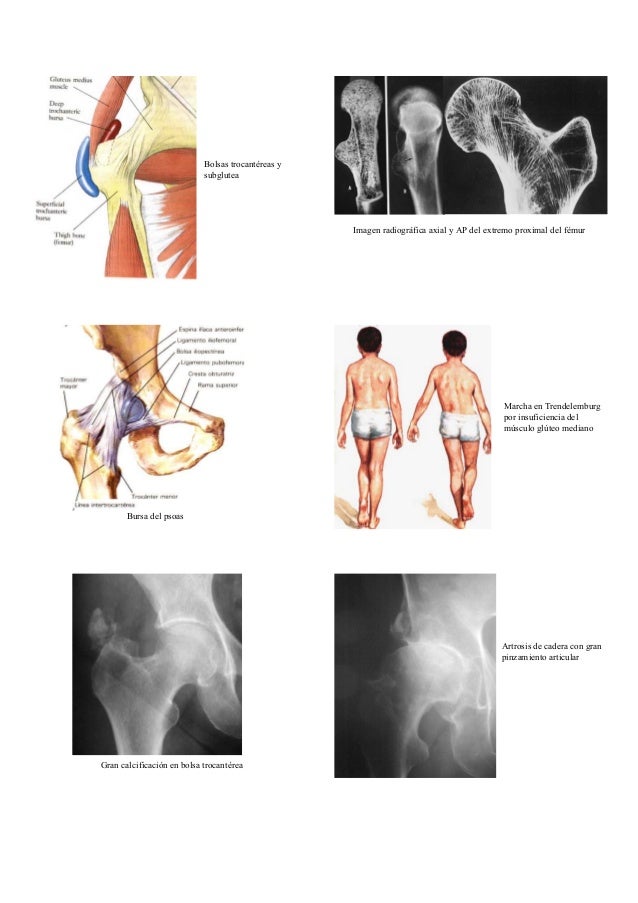

WebLas mejores plantillas para la artrosis. La artrosis de cadera se produce gradualmente con el paso de los aƱos, ya que el cartĆlago amortiguador de la. WebLas plantillas ortopĆ©dicas pueden tener un efecto benĆ©fico para aliviar los dolores artrósicos de la rodilla, el pie, los tobillos y la cadera. Permiten amortiguar los golpes y reducir la. WebEnvĆos Gratis en el dĆa ComprĆ” Plantillas Para Artrosis en cuotas sin interĆ©s! ConocĆ© nuestras increĆbles ofertas y promociones en millones de productos. ConocĆ© nuestras. WebLa osteoartritis de cadera, coloquialmente llamada artrosis de cadera, es una patologĆa articular, muy incapacitante cuando llega a estados muy avanzados. Las. WebLa artrosis es la enfermedad crónica en la que se «desgasta» una articulación. Los anglosajones la llaman la osteoartritis o artritis. Artrosis no es lo mismo.

Artrosis de Cadera - Copia | Osteoartritis | CartĆlago

AquĆ Artrosis de cadera.ppt | Cadera | Osteoartritis | Prueba gratuita de 30 Ćltimo

Discusión Artrosis de Cadera | PDF | Osteoartritis | Rodilla tendencias